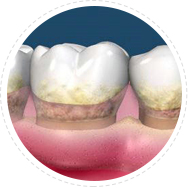

针对牙周炎、不良修复体导致的牙周袋, 龈下刮治术通过精密器械,清除根面结石和菌斑创口小愈合快,但建议根治牙周炎或更换不良修复体,才能治本

适应症:牙龈炎、牙周炎、 牙周袋、不良修复体引起的口臭